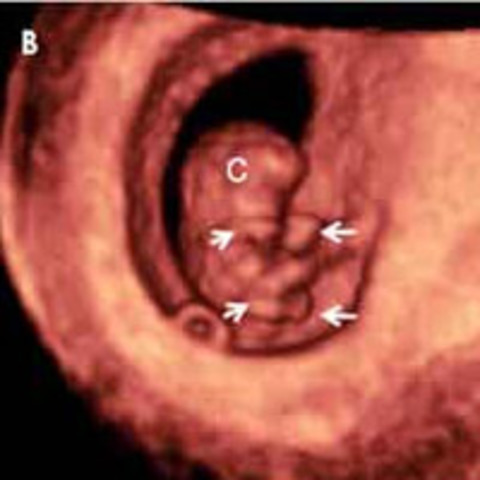

• Semana 7

Semana 7

Están empezando a aparecer los vestigios de las piernas y los brazos en forma de cuatro pequeños apéndices microscópicos. El embrión sigue teniendo una cabeza muy grande en comparación con el resto del cuerpo y una extremidad opuesta en forma de pequeña cola curvada.os pulmones tienen un bronquio primario para permitir el paso del aire. El cerebro se divide en dos hemisferios cerebrales y va aumentado de tamaño. Empiezan a aparecer las fosas nasales y las órbitas de los ojos.Se desarrollan intes